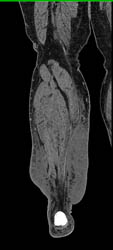

Cellulitis